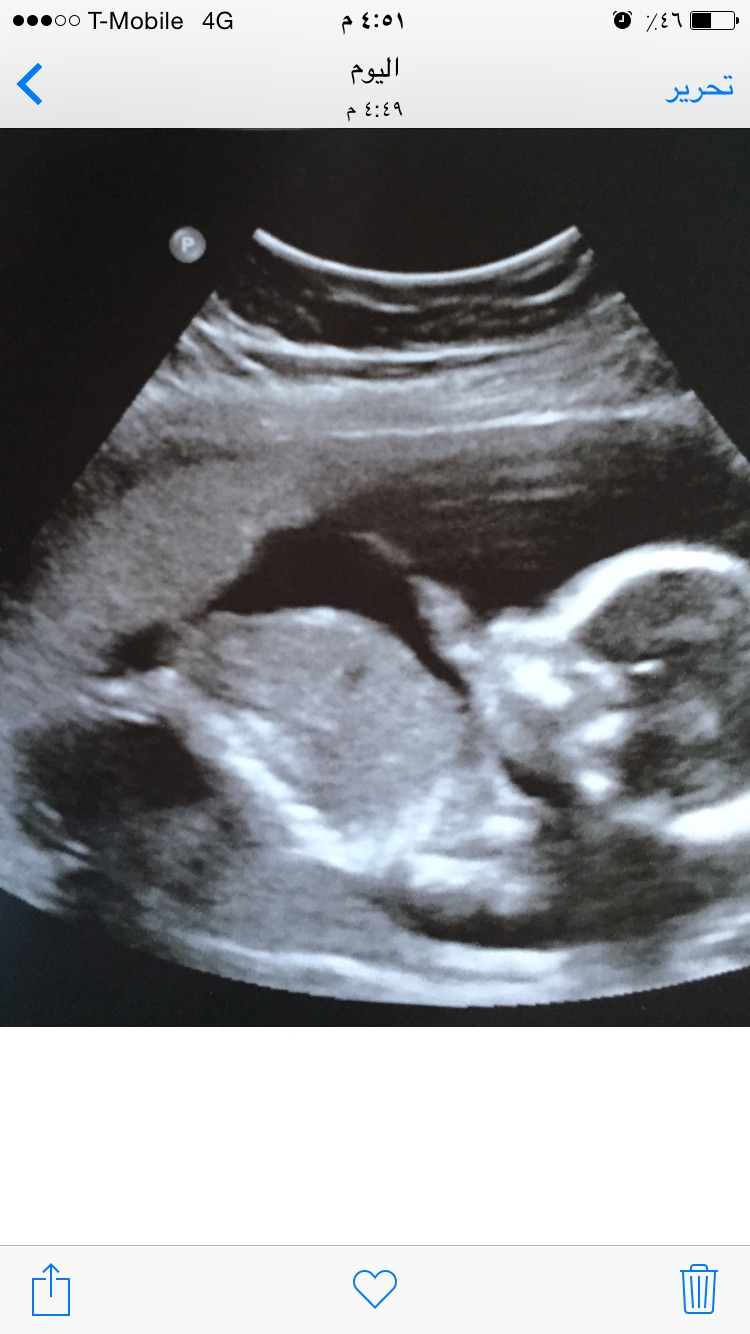

And here are the 19w+2d pictures

Attachment 28677

Attachment 28679